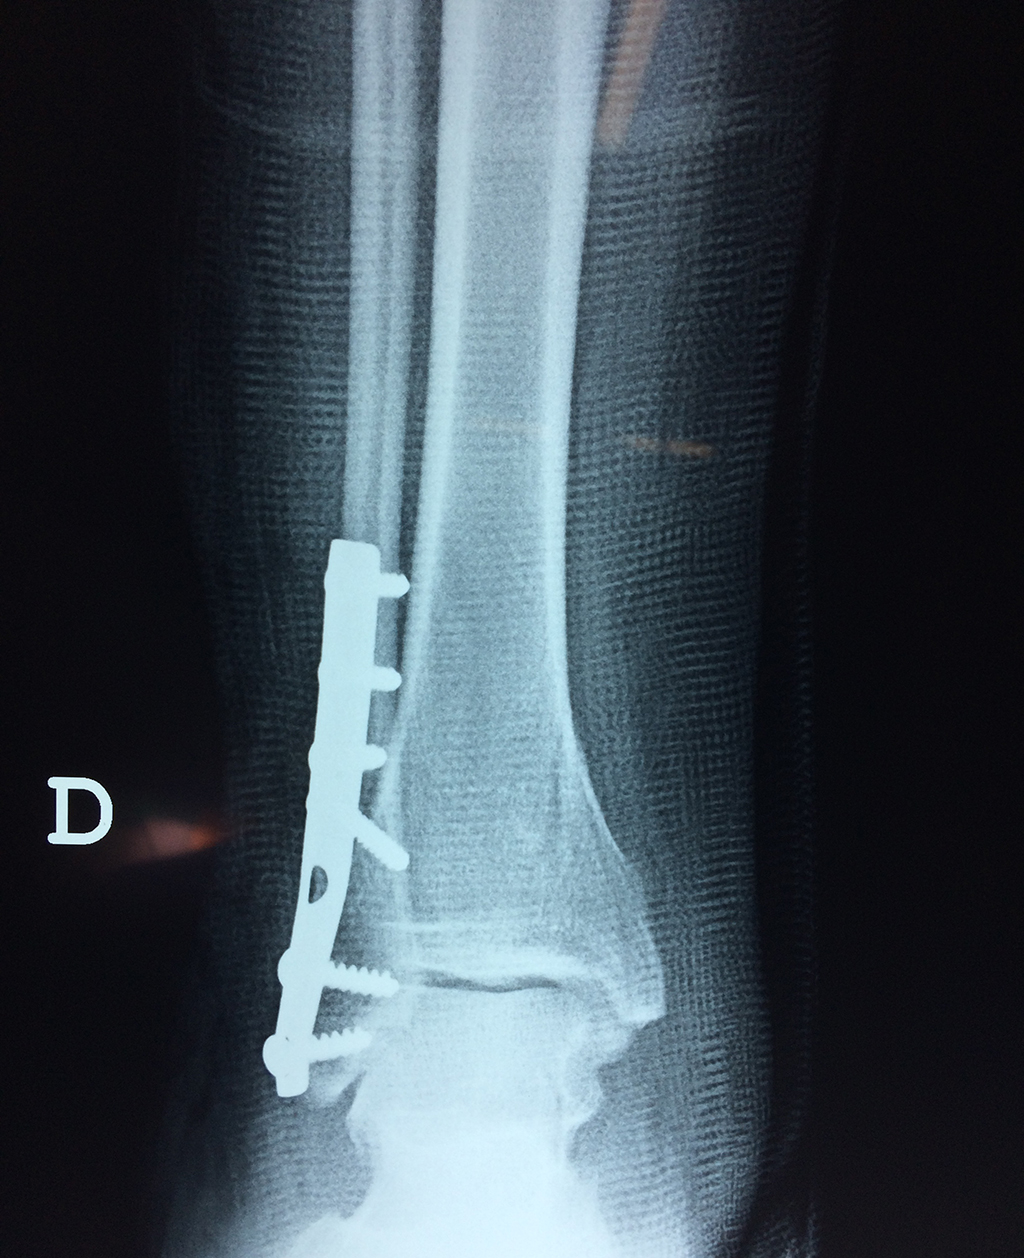

Cuando se necesita cirugía, es probable que esta implique el uso de clavijas de metal, tornillos o placas para sostener los huesos en su lugar mientras la fractura se consolida. Los elementos de soporte pueden ser temporales o permanentes.

- Los extremos de los huesos están desalineados entre sí (desplazados).

- La fractura se extiende hasta la articulación del tobillo (fractura intra-articular).